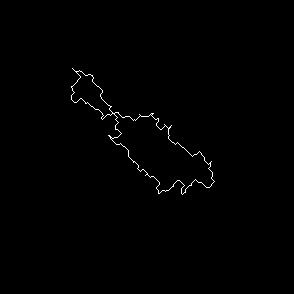

Original frames was obtained from U-118 cell line sample set. U-118 is human glyoblastoma cells widely used as model for drug testing. Also it has fibroblast like morphology and highly dynamic shape change pattern. From original microscopic images we created sets of frames containing single cell with manually outlined borders as ground truth dataset. This sets were used to have primary evaluation of segmentation successiveness. In result of described batch segmentation we obtained outline masks for each image in sequence with different accuracy of segmentation. Frames 1, 2, 9, 15, 20, 25, 40 of U-118 cell line sequence at Fig.2 an example of drastic changes of segmentation accuracy compared to manual perimeter detection.

(g) Frame 1, algorithm segmentation

Refer to caption

(h) Frame 2, algorithm segmentation

(i) Frame 9, algorithm segmentation

(j) Frame 15, algorithm segmentation

(k) Frame 25, algorithm segmentation

(l) Frame 40, algorithm segmentation

(m) Frame 1, manual segmentation

(n) Frame 2, manual segmentation

(o) Frame 9, manual segmentation

(p) Frame 15, manual segmentation

(q) Frame 25, manual segmentation

(r) Frame 40, manual segmentation

Figure 2: Original images sample sequence, results of algorithm processed and manually outlined cell contour. The image i and j of sequence show bad segmentation accuracy compared to manually outlined images, while rest of sequence has acceptable level.